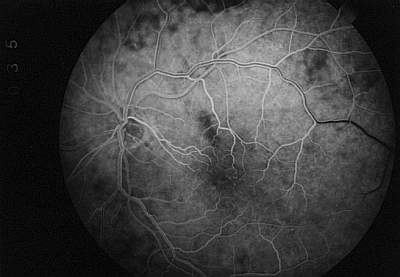

Die Spätphase der Aderhautfluoreszenz unterscheidet sich nicht mehr von der normalen Fluoreszenzangiographie. In der diffusen Färbung der Choriokapillaris stellen sich die jetzt fluoreszeinfreien Aderhautgefäße als unscharfe, dunkel Streifen dar (Negativ-Darstellung der Aderhautgefäße). Fluoreszenzangiographische Befunde, wie z.B. pathologische Hyperfluoreszenzen oder Fensterdefekte, können genauso wie bei der konventionellen Angiographie erhoben werden (Abb. 15) . |

Abb. 15 Phase der diffusen Aderhautfüllung (FLADOP, IOD = 45 mmHg) |